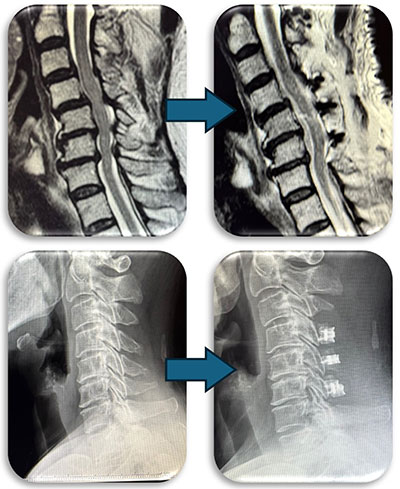

(代表例①)

頚部の脊柱管狭窄症に対して、首の後ろから手術する椎弓形成術を行なった症例です。脊柱管と呼ばれる脊髄が通るトンネルの屋根部分にあたる椎弓を縦割し観音開きで広げ、さらに新しい屋根の代わりとなる金属プレートを被せることによって脊柱管を広げます。